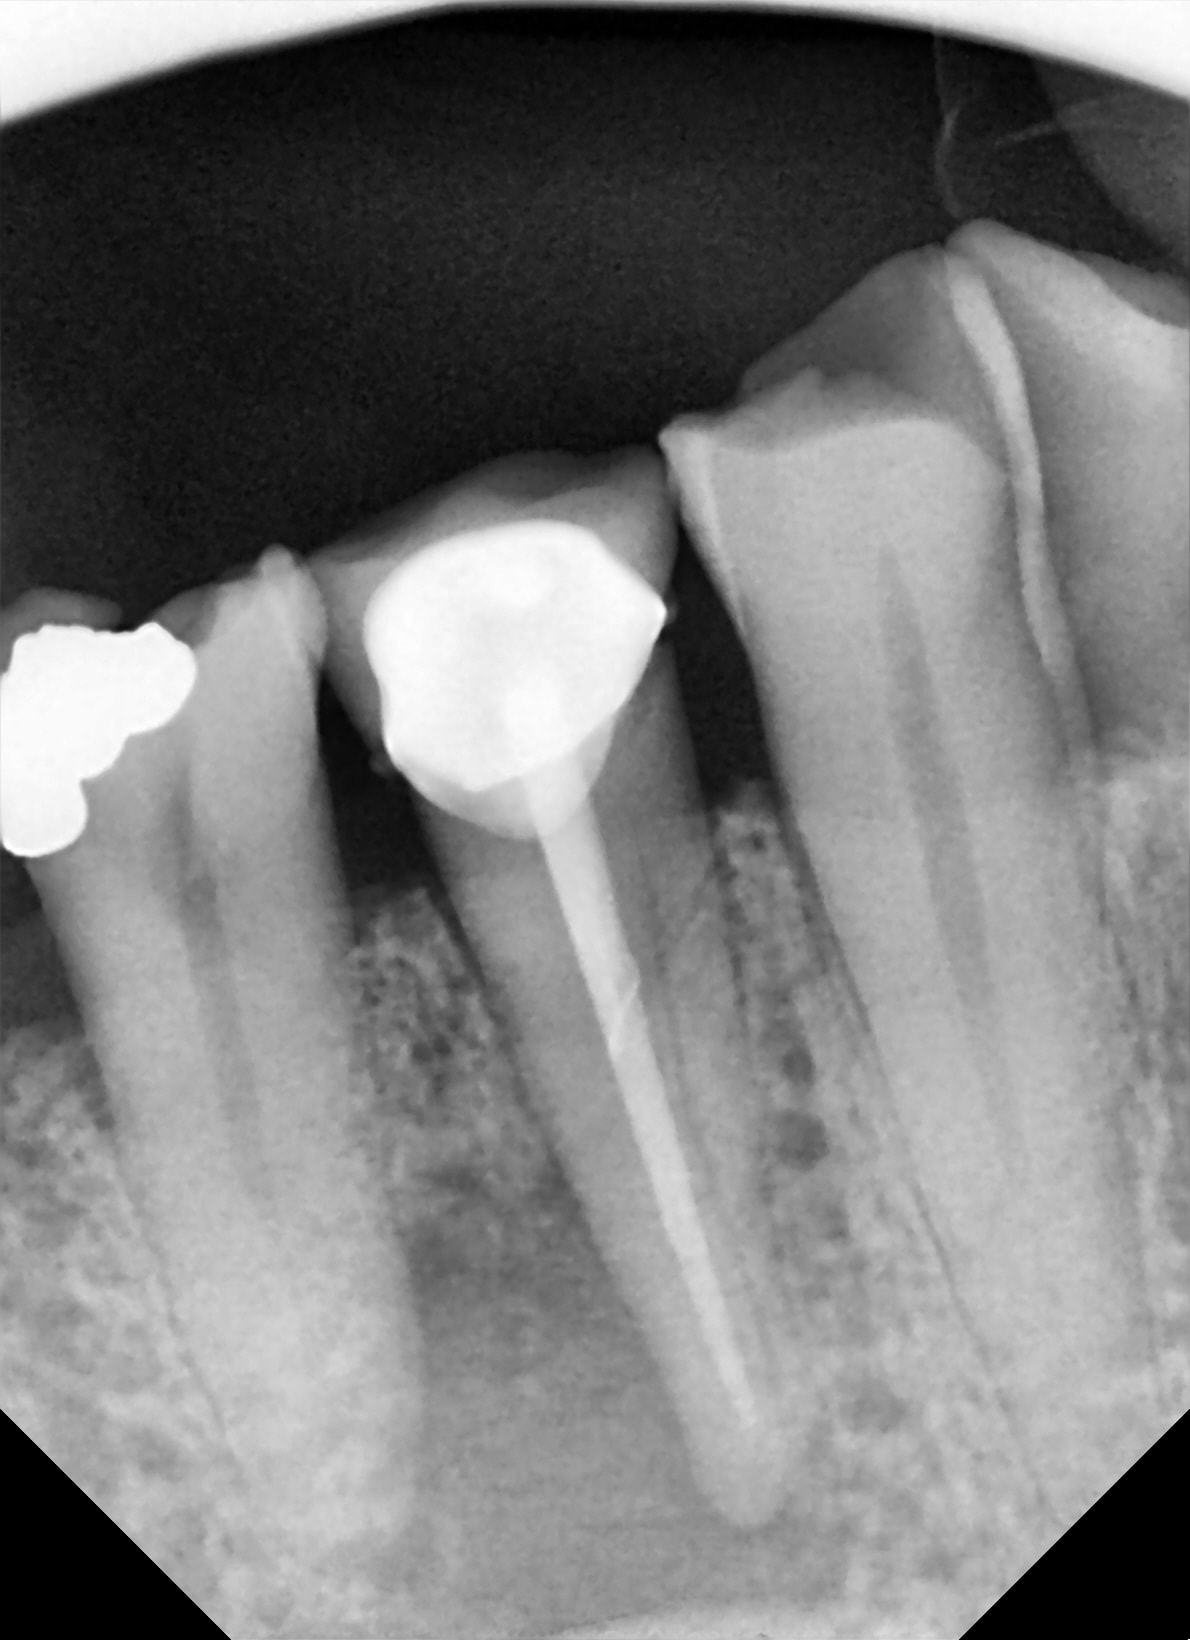

05/02/2018 à 11h23

37

apres une endo de sauvage ,bien bourrée au compactor , 1 petit aller retour pour cette 37 .

pratique pour detartrer la face distale :-))

je vous tiens au courant .